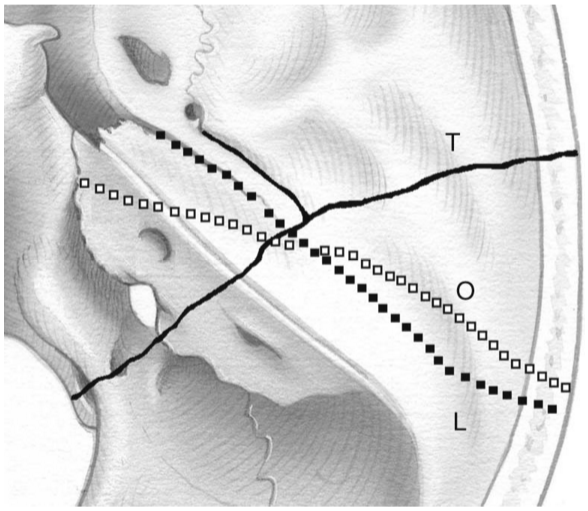

Temporal bone fractures are classically described as either longitudinal or transverse; however, most fractures are actually in an oblique or mixed pattern (Figure 45-1). They can also be described as otic capsule-sparing or disrupting to emphasize the functional sequelae of the fracture, and other authors have described them according to the portion of the temporal bone involved (squamous, tympanic, mastoid, and petrous).

Figure text: Temporal bone fractures, longitudinal (L), transverse (T), and oblique (O).